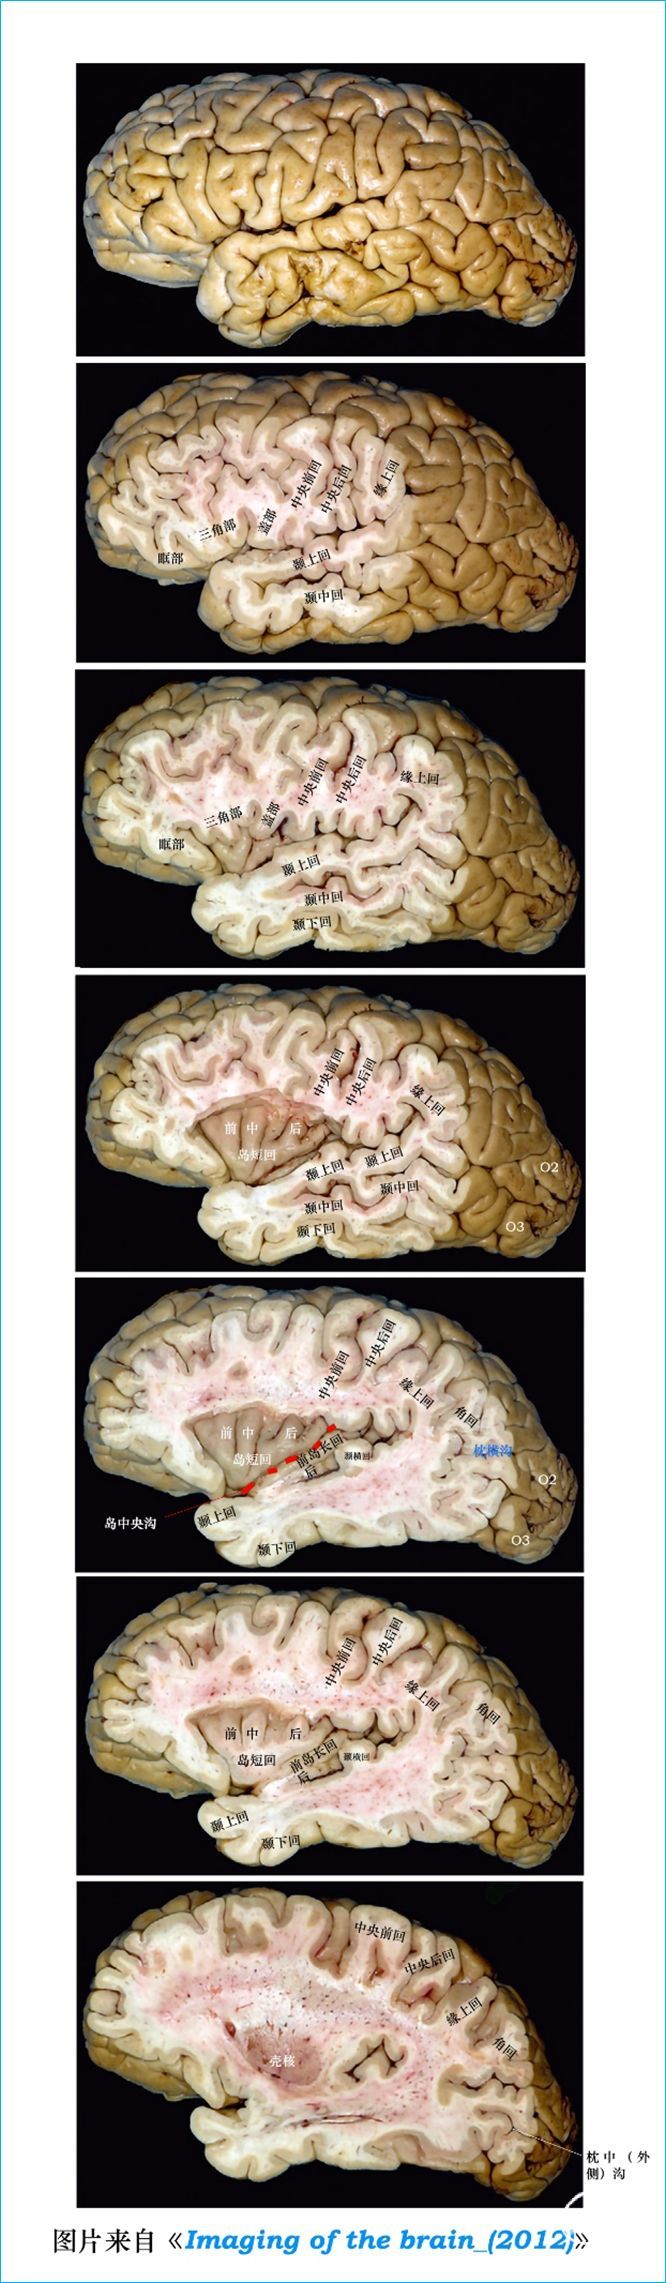

T2WI反相图学下的颅脑断层解剖(吴老师亲自手动标准)以及标本断层解剖,满满干货,坐在小板凳上,一起学习吧...如有标注错误,望大家多多批评指正。MR图像全部来自黄山昌仁医院的3.0TMRI。

大脑半球标本连续切片断层解剖

02